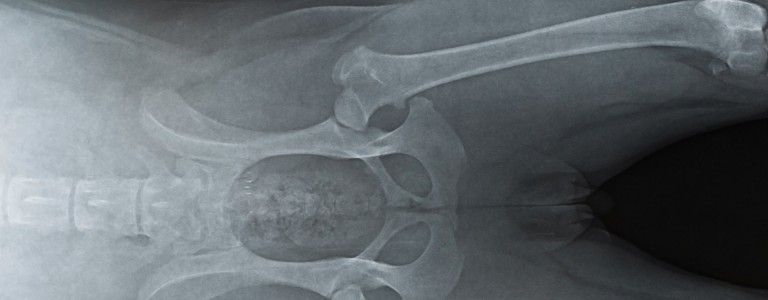

Vice rédhibitoire chien dysplasie coxo fémorale

Cette atteinte correspond à une malformation progressive de la hanche pouvant se manifester à n'importe quel stade de vie.

En général on remarque la dysplasie plutôt chez le chien adulte.

Les symptômes peuvent être une démarche ondulante, un déplacement des membres postérieurs en simultanée jusqu'à une raideur avec ou sans boiterie.

Cette maladie peut exister chez la majorité des races mais est surtout fréquente chez les plus grands gabarits.

La dysplasie favorise l'apparition d'arthrose.

Cette pathologie est principalement congénitale mais peut également être causée par des facteurs externes durant la croissance.

Un excès d'exercice, des mauvaises sollicitations, un excès pondéral et une alimentation non adaptée au chiot peuvent provoquer une dysplasie.

En fonction du stade de la dysplasie et si celle-ci est bien suivie, l'animal peut tout de même avoir une qualité de vie décente.

Il existe un dépistage précoce afin de limiter la dégénérescence (régime alimentaire, activité physique, traitement médical ou chirurgical).

A l'adoption d'un chien de grande taille, il est conseillé d'effectuer une radio des hanches avant 1 an même sans signe clinique afin d'être en mesure d'effectuer une action en rédhibition ou de consulter le vendeur.

Seuls les clichés médicaux pris avant les un an de l'animal peuvent être pris en considération.